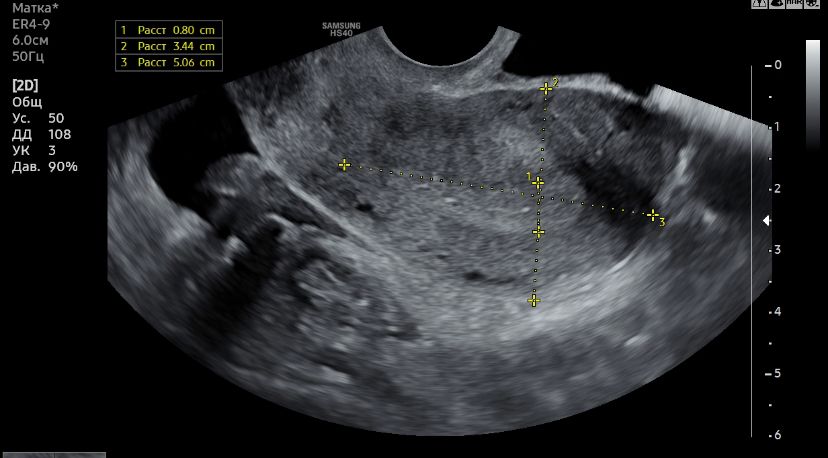

Узи и киста

Сказали киста желтого тела, но я не сильно доверяю, до этого она говорила что обычная киста от фоллика